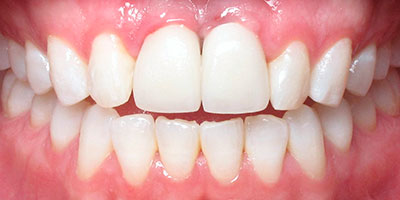

Posteriormente con citas de revisión periódicas damos tiempo de integración de 6 meses y procedemos a rehabilitar el caso con coronas de cerámica.